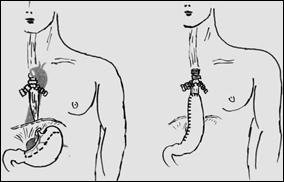

Рис. 5. Схема выкраивания трансплантата из большой кривизны желудка в антиперистальтической позиции по Гаврилиу. Выполнено обходное шунтирование стриктуры нижнегрудного отдела пищевода (вариант 1 – без резекции пищевода, вариант 2 – с резекцией рубцово измененного пищевода)

Рис 6. Схема доступов для резекции пищевода с одномоментной пластикой целым желудком при операции Льюиса и операции, схема которой изображена на рис. 5.